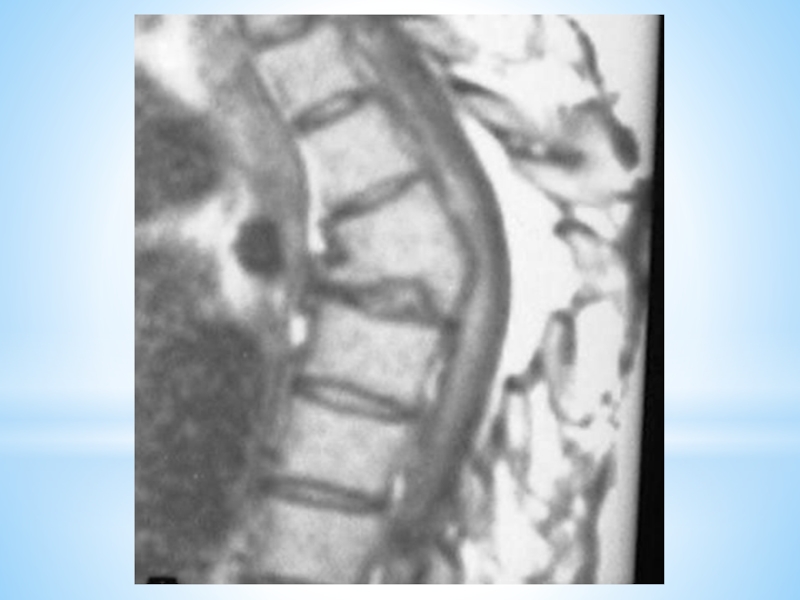

Слайд 40Р Е Н Т Г Е Н Д И А Г

Н О С Т И К А

В спондилитической фазе рентгено­логическая картина может быть ограниченной в виде изолированной каверны с разрушением компактных пластин тела позвонка, снижением высоты соседнего диска и локальным кифозом.

На передней или боковой поверхности позвоночника определяется уплотнение мягких тканей, что указывает на формирование натёчного абсцесса. При наличии при­ знаков компрессии спинного мозга показана миелография для уточнения локализации компрессирующего фактора, его протяженности и степени выраженности вертебро-медуллярного конфликта.

Аналогичную информацию можно получить методами КТ и МРТ.

В постспондилитической фазе рентгенологически присутствуют признаки сращения пораженных позвонков («костный блок»), исчезают признаки натёчных абсцессов. Однако по результатам рентгеновской томографии, КТ и МРТ можно выявить сохраняющиеся ограниченные очаги в телах позвонков или остатки натёчных абсцессов